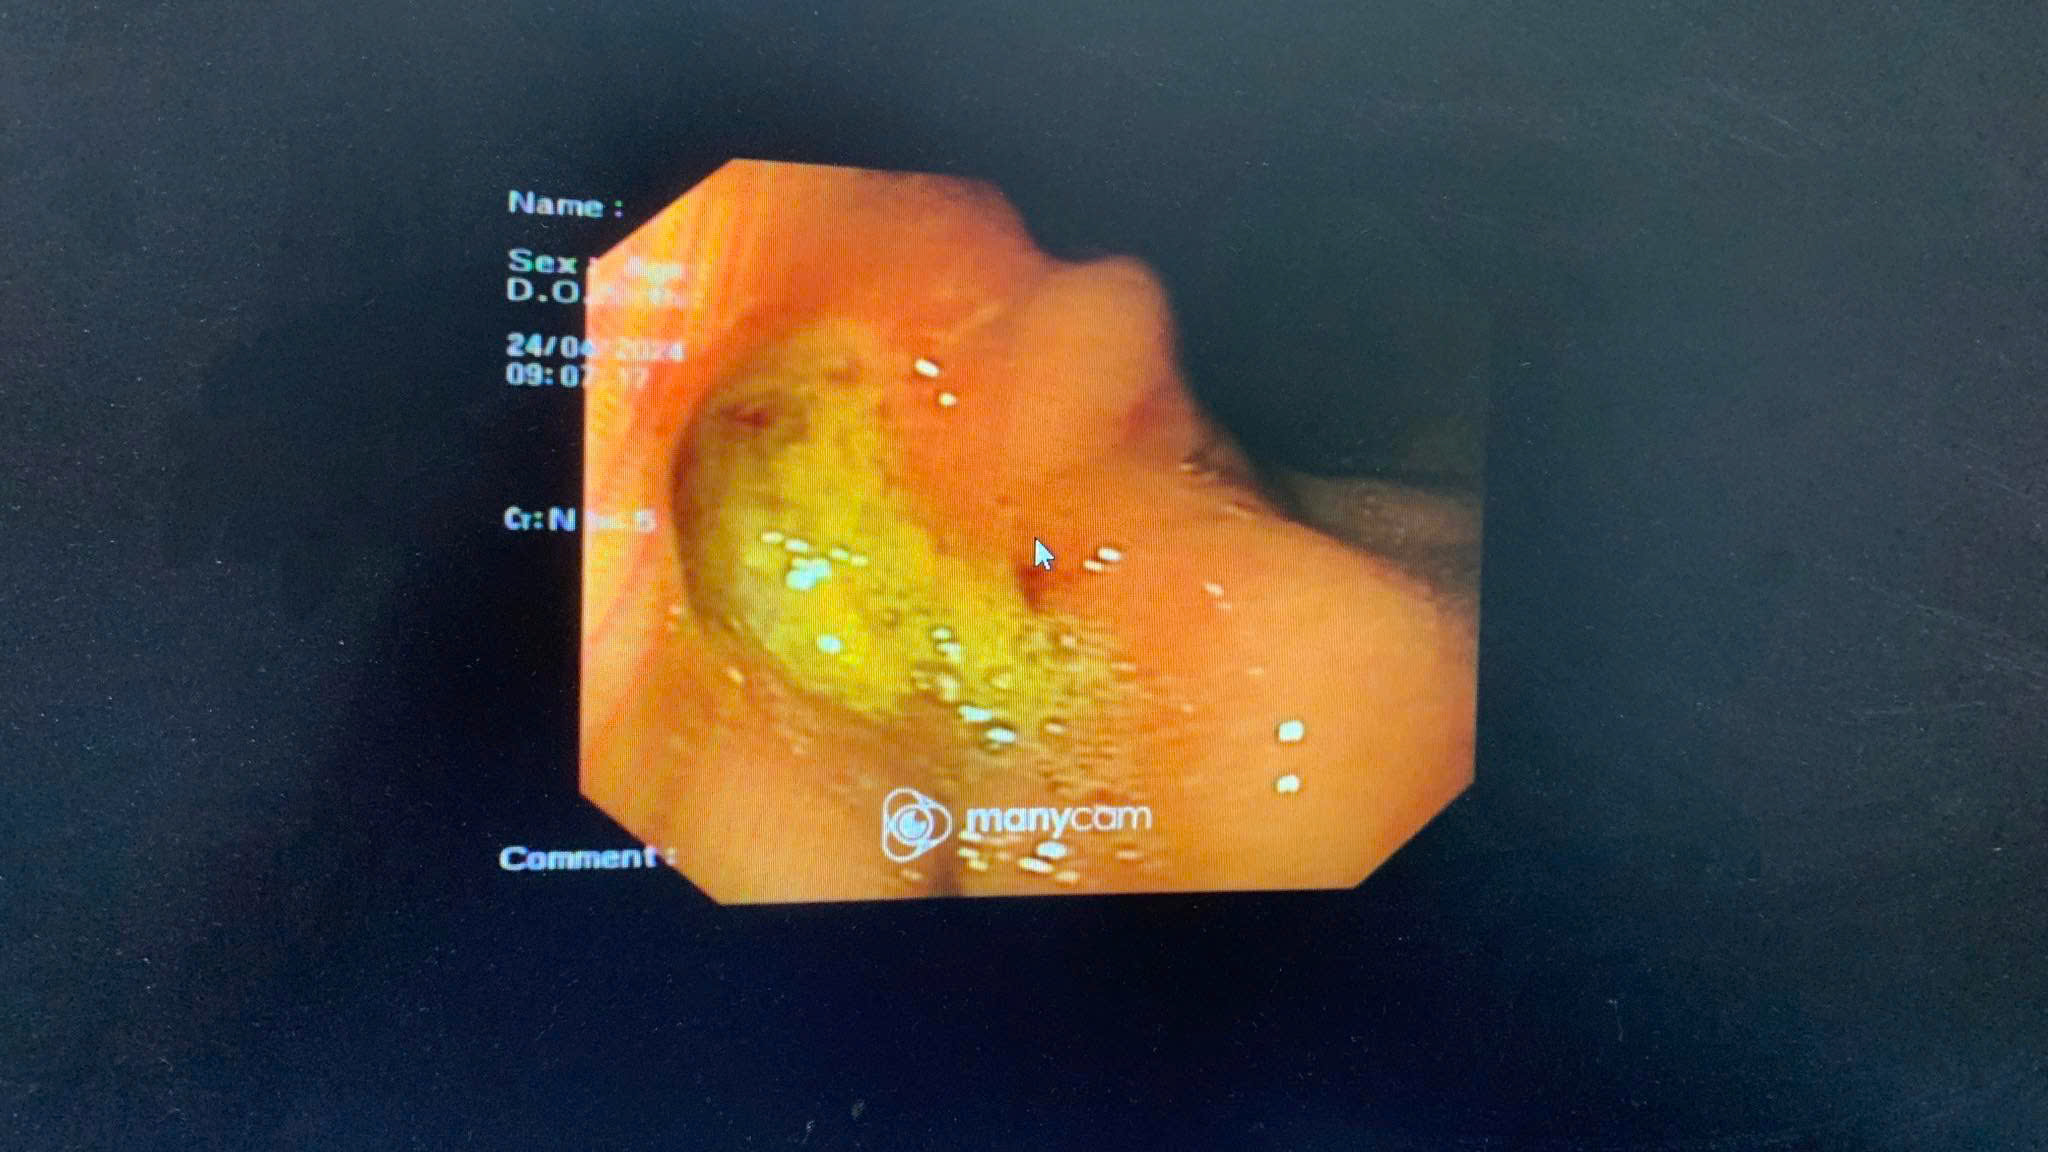

Nội soi tiêu hoá là kỹ thuật giúp bác sĩ quan sát trực tiếp niêm mạc ống tiêu hoá, phát hiện sớm các tổn thương như viêm loét, xuất huyết, polyp hay khối u. Đây là phương pháp hiệu quả nhất để tầm soát và phát hiện sớm ung thư dạ dày, đại tràng, mang lại cơ hội điều trị thành công cao hơn cho người bệnh.

Một trong những lo lắng phổ biến là “nội soi rất đau và khó chịu”. Trên thực tế, với kỹ thuật nội soi gây mê nhẹ, người bệnh hoàn toàn không cảm thấy đau đớn hay khó chịu trong suốt quá trình thực hiện. Thời gian nội soi nhanh, chỉ từ 10–15 phút, sau đó có thể nghỉ ngơi ngắn và sinh hoạt bình thường.